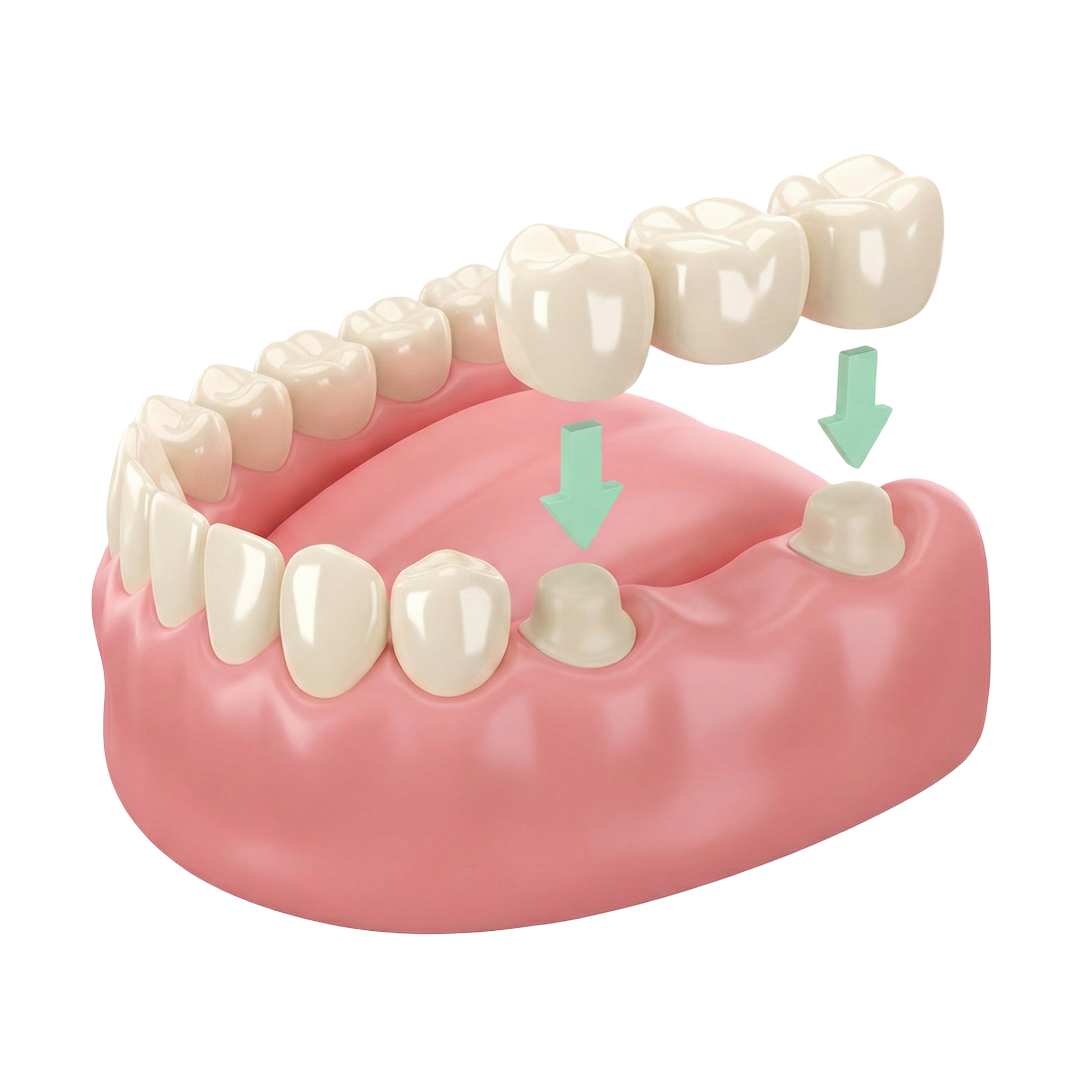

What is a Bridge?

A bridge is a dental restoration used to replace one or more missing teeth by anchoring onto the adjacent teeth. The teeth on either side of the gap are trimmed, and the bridge is permanently cemented in place. Compared to dentures, bridges are more comfortable and are usually more affordable than dental implants.

Preparation for a Bridge

Gap (missing tooth)

Reshaped adjacent teeth

Bridge